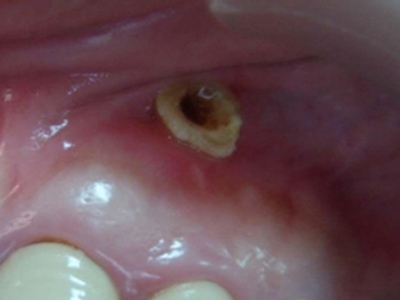

牙龈癌在口腔癌中仅次于舌癌而居第2位,组织学类型绝大多数为分化程度较高的鳞状细胞癌。牙龈癌好发于前磨牙区及磨牙区,下牙龈癌较上牙龈癌为多见,上下之比为2:1。牙龈癌发病年龄多为40-60岁,男性多于女性。

牙龈癌多源于牙间乳头及龈缘区,溃疡呈表浅、淡红,以后可出现增生。由于黏骨膜与牙槽突附着甚紧,较易早期侵犯牙槽突骨膜及骨质,进而出现牙松动,并可发生脱落。X线片可出现恶性肿瘤的破坏特征虫蚀状不规则吸收。

牙龈癌常发生继发感染,肿瘤伴以坏死组织,触之易出血。体积过大时可出现面部肿胀,浸润皮肤。